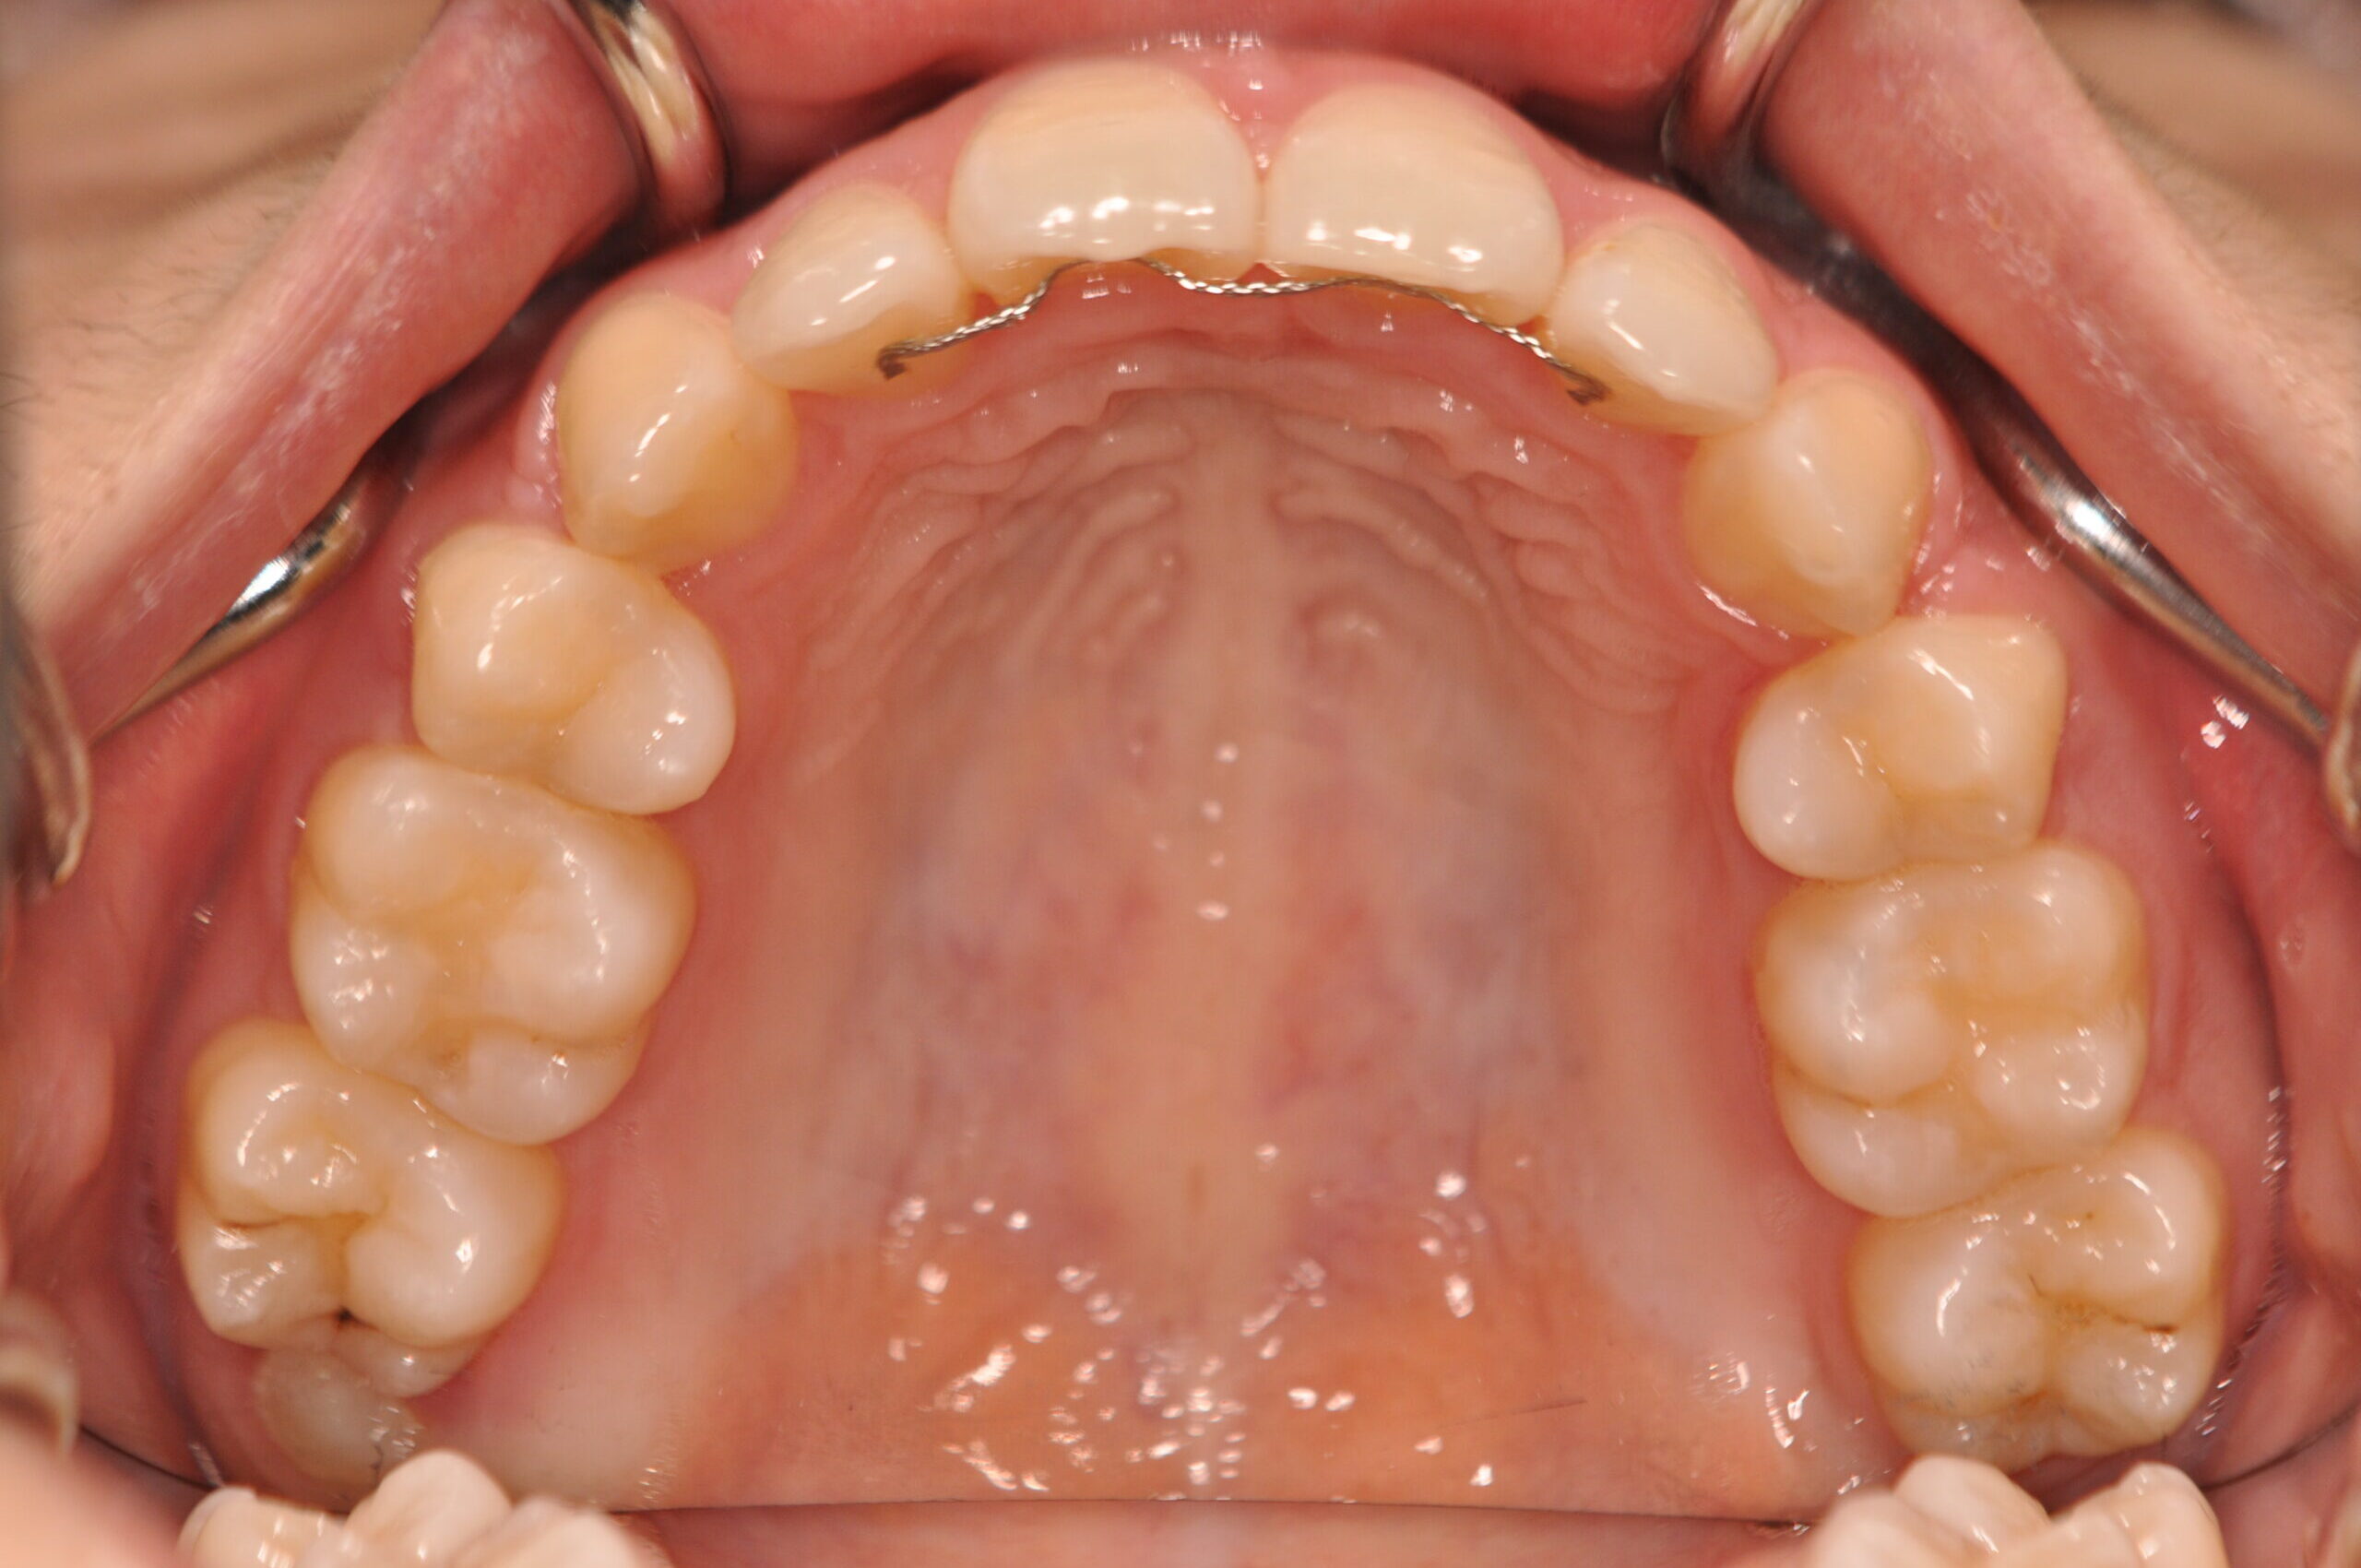

でっ歯(抜歯)【2247】

初診時

年齢

20歳 性 別 女性

治療期間 2年1ヶ月 費 用 矯正施術料:1,000,000円

調整料:4,000円

治療内容の詳細 初診時20歳の女性で、出っ歯、歯のがたつきを気にされ来院しました。

検査の結果、上下顎前歯部叢生を伴うアングルⅠ級不正咬合と診断しました。

治療としては、上下左右第一小臼歯を抜歯の上、セルフライゲーションブラケット装置(デーモンシステム)と

マウスピース矯正装置(インビザライン)で配列を行いました。

この際、上顎に歯科矯正用アンカースクリューを設置し上顎前歯部後退時の土台としました。

治療期間は2年1ヶ月でした。